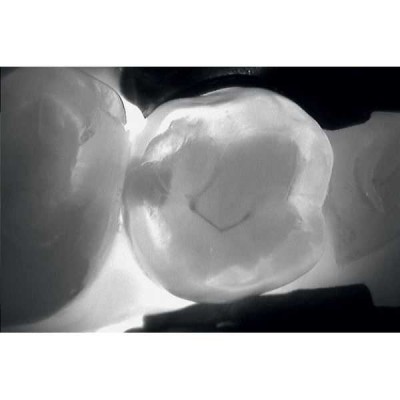

KaVo DIAGNOcam позволяет визуализировать их на аппроксимальных и окклюзионных поверхностях зубов и обеспечивает проведение диагностики вторичного кариеса (при небольшом размере пломбы).

Весь секрет заключается в технологии DIFOTI за счет генерируемого прибором трансилюминационного (трансиллюминация - яркое сквозное освещение) лазерного излучения в нерентгеновском диапазоне волн. Если объяснять это простым языком, то это излучение, занимающее диапазон между видимым светом и рентгеновским диапазоном, которое проходит сквозь твердые ткани зуба, при этом области, не пропускающие свет (например, области кариозного поражения) отображаются в виде затемненных на общем фоне участков.

Цифровая видеокамера фиксирует результат и передает изображение на экран в режиме реального времени.